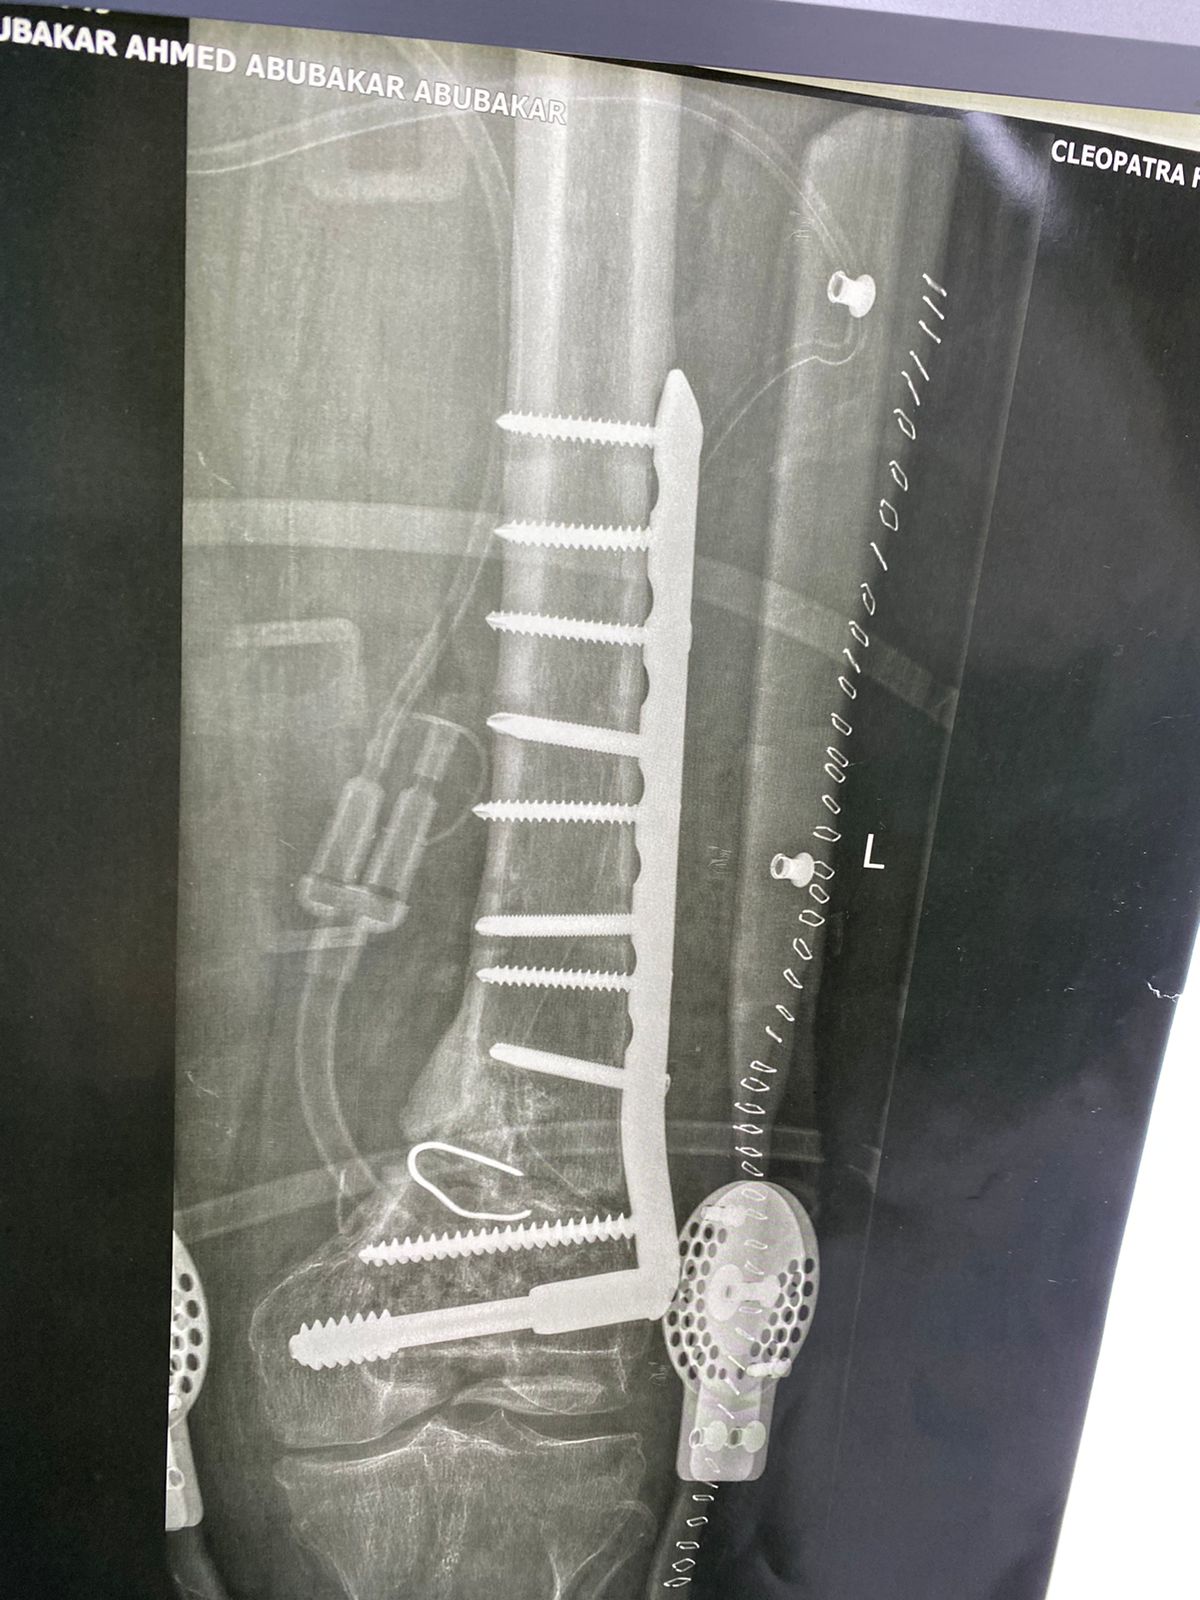

صورة اشعة تبين شريحة تم تركيبها بشكل خاطئ ترتب عليها اعوجاج بالركبة

الأشعات بعد الجراحة مباشرة و الاشعات الاخيره بعد الجراحة ب ٦ أشهر